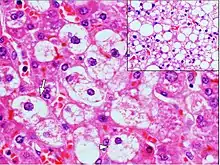

Microvesicular steatosis

Microvesicular steatosis is characterized by small intracytoplasmic fat vacuoles (liposomes) which accumulate within hepatocytes.[9] It is associated with a wide variety of conditions, including alcoholism, drug toxicity of several medications, delta hepatitis (in South America and Central Africa), sudden childhood death, congenital defects of fatty acid beta oxidation, cholesterol ester storage disease, Wolman disease and Alpers syndrome.[10]

Histologically, steatosis is physically apparent as lipid within membrane bound liposomes of parenchymal cells.[2] When this tissue is fixed and stained to be better viewed under a microscope, the lipid is usually dissolved by the solvents used to prepare the sample. As such, samples prepared this way will appear to have empty holes (or vacuoles) within the cells where the lipid has been cleared. Special lipid stains, such as Sudan stains and osmium tetroxide are able to retain and show up lipid droplets, hence more conclusively indicating the presence of lipids. Other intracellular accumulations, such as water or glycogen, can also appear as clear vacuoles, therefore it becomes necessary to use stains to better determine what substance is accumulating.

Histological section of a mouse's liver showing severe steatosis. The clear vacuoles contained lipid in life; however, histological fixation caused it to be dissolved and hence only empty/clear spaces are seen.

Histological section of a mouse's liver showing severe steatosis. The clear vacuoles contained lipid in life; however, histological fixation caused it to be dissolved and hence only empty/clear spaces are seen. Micrograph of fatty liver showing lipid steatosis. H&E stain.

Micrograph of fatty liver showing lipid steatosis. H&E stain. Steatosis with a centrilobular pattern, which is the general tendency for steatosis in adults.[11]